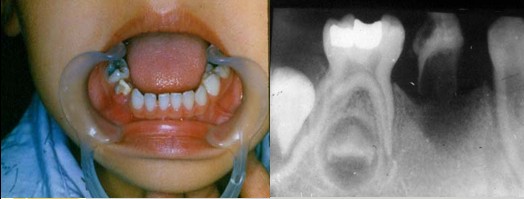

解析: 牙齿异位萌出

牙齿异位萌出的临床表现包括:第一恒磨牙近中边缘嵴阻生于第二乳磨牙远中牙颈下,X线:第二乳磨牙远中根牙颈部吸收区或非典型性吸收,第一恒磨牙近中边缘嵴嵌入;第二乳磨牙间隙开始缩小。治疗措施包括:早期临床观察,钢丝结扎分离,截冠加金属冠修复,拔除第二乳磨牙,导萌器引导恒牙萌出。

解析: 钢丝结扎分离